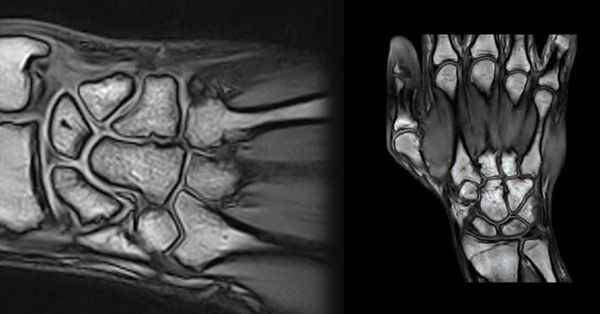

(Слева) На фронтальной МРТ Т1ВИ определяется склеротическая неровность проксимальной поверхности трехгранной кости. Длинный и крючковидный шиловидный отросток локтевой кости врезается в тыльную медиальную поверхность трехгранной кости, повреждая хрящ, что приводит к субхондральному склерозу.

(Справа) На заднепередней рентгенограмме определяется незначительный импичмент проксимальной поверхности трехгранной кости, покрытой выраженным кортикальным слоем, округленным основанием шиловидного отростка локтевой кости с несросшимся переломом. Постоянная боль может быть обусловлена непосредственным сдавливанием кости или сопутствующим разрывом треугольного фиброзно-хрящевого комплекса.